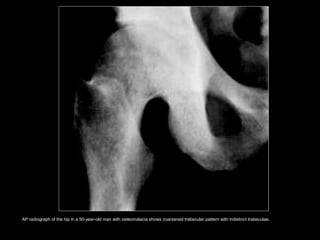

• The M/C radiologic sign is generalized

osteopenia.

• Coarsened and indistinct bony trabeculae.

• Poorly defined interfaces between cortical and

trabecular bone.

• Looser's zone, or pseudofracture. (more

specific but less common)

AP radiograph of the hip in a 50-year-old man with osteomalacia shows coarsened trabecular pattern with indistinct trabeculae.